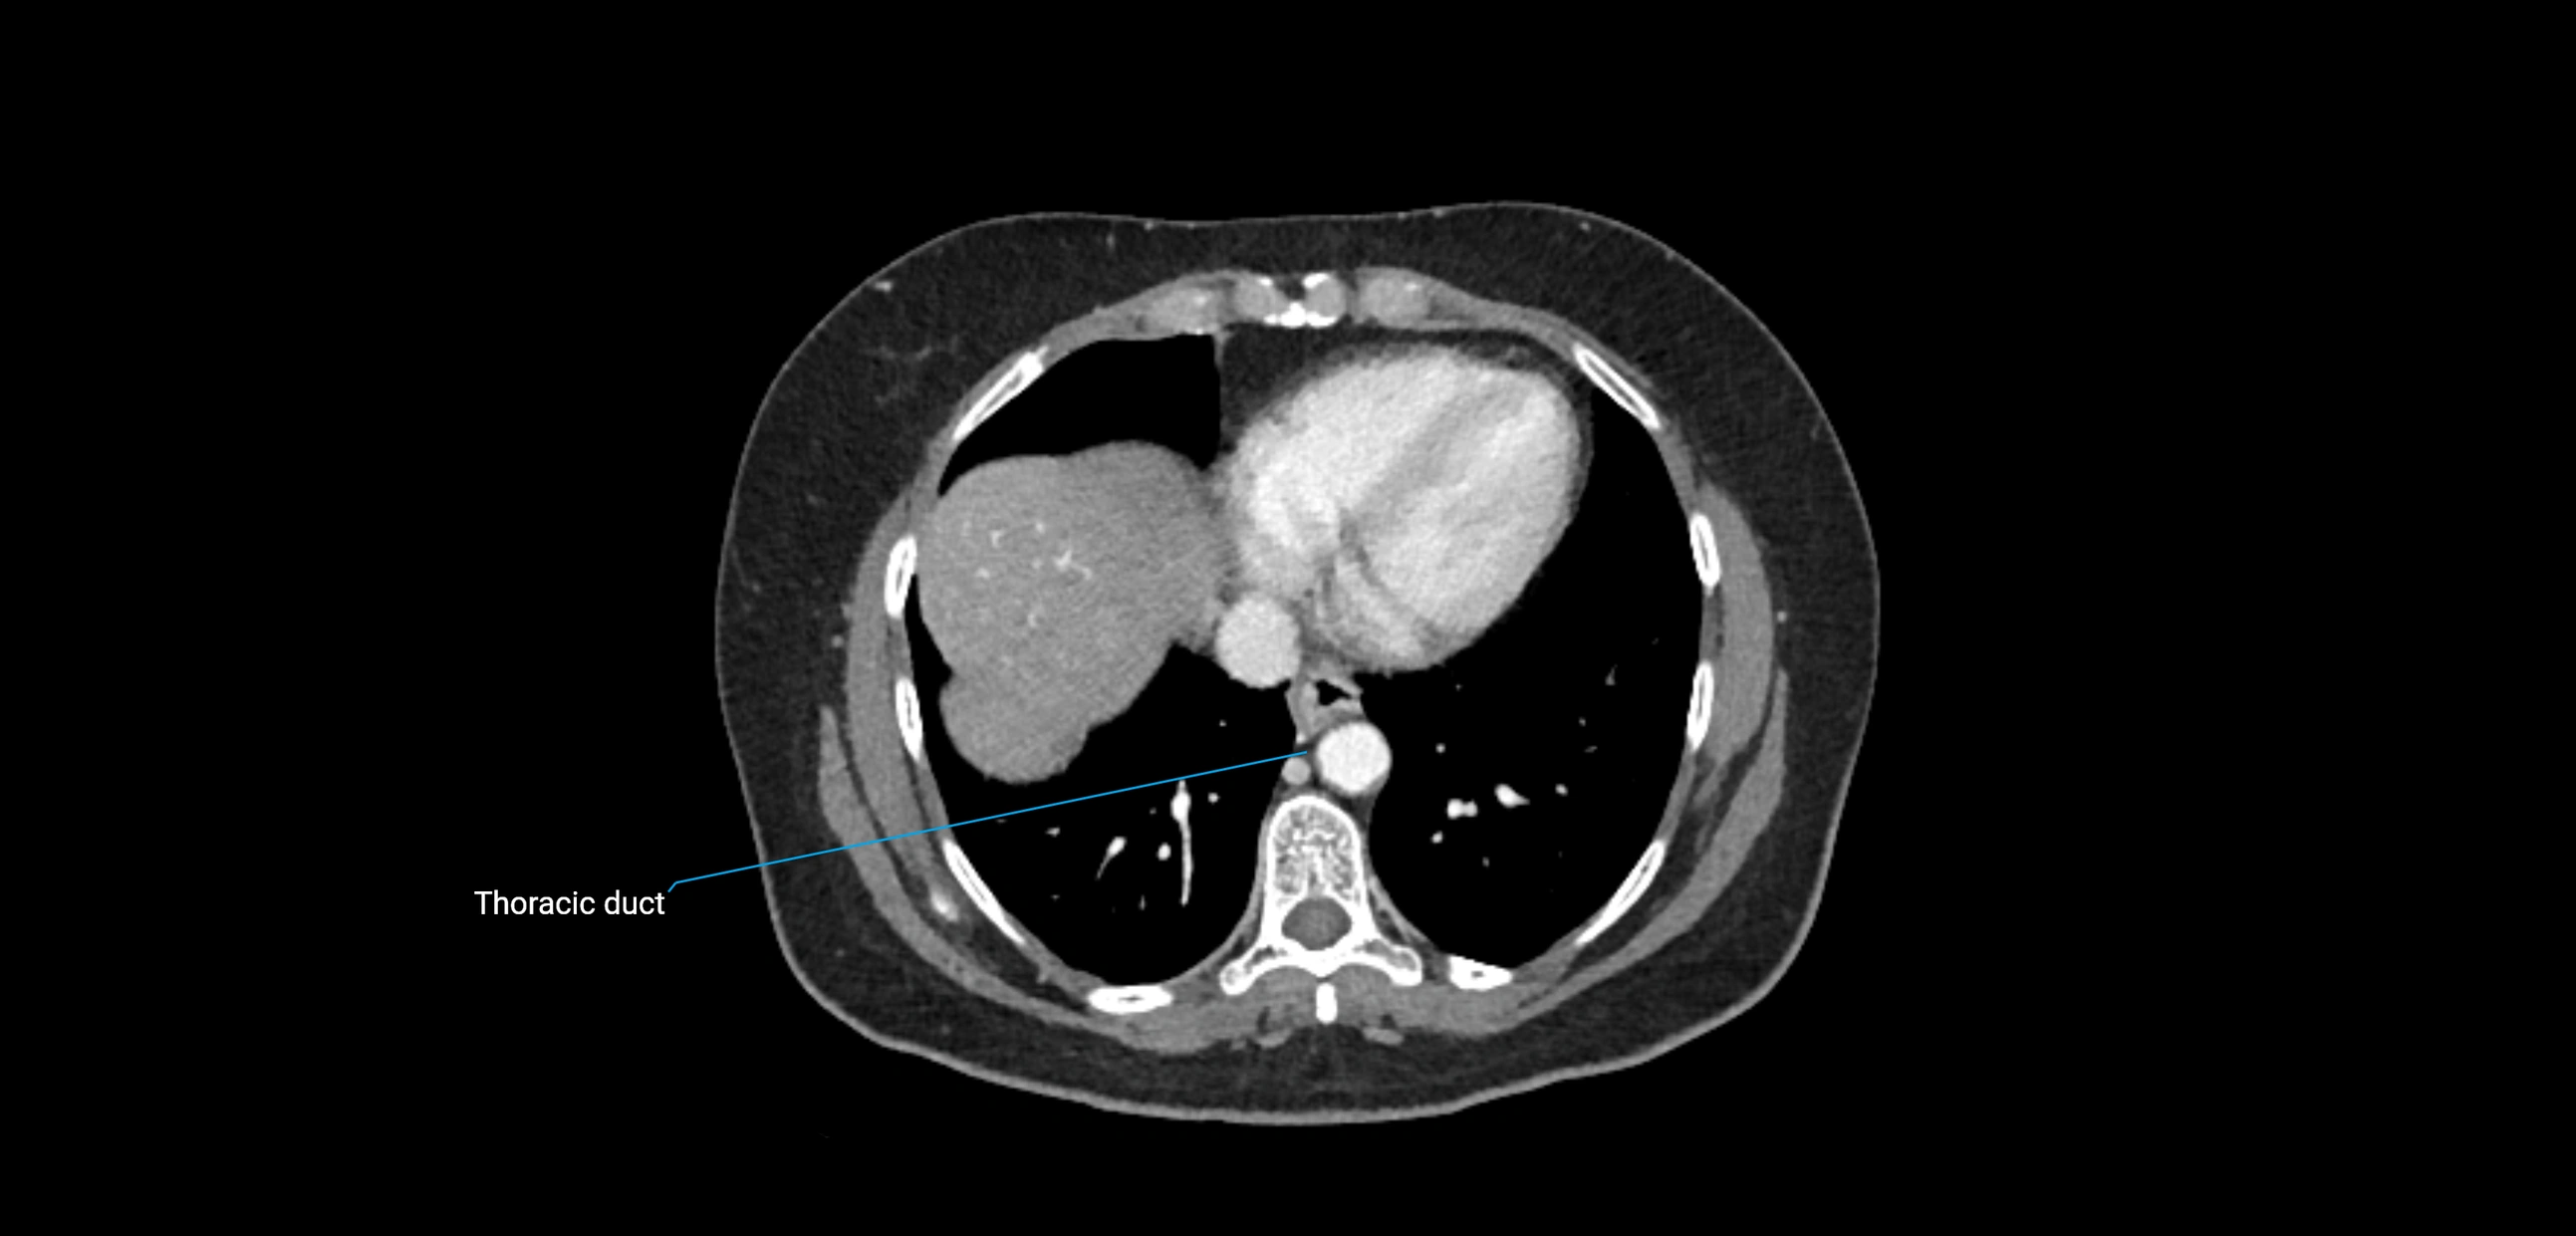

These nodes receive lymph from a wide range of abdominal and pelvic structures. Specifically, they drain lymph from the kidneys, suprarenal glands, gonads (testes/ovaries), uterus, uterine tubes, and pelvic organs, before converging into the lumbar lymphatic trunks, which terminate in the cisterna chyli → thoracic duct.

• Provide a major pathway to the cisterna chyli and thoracic duct